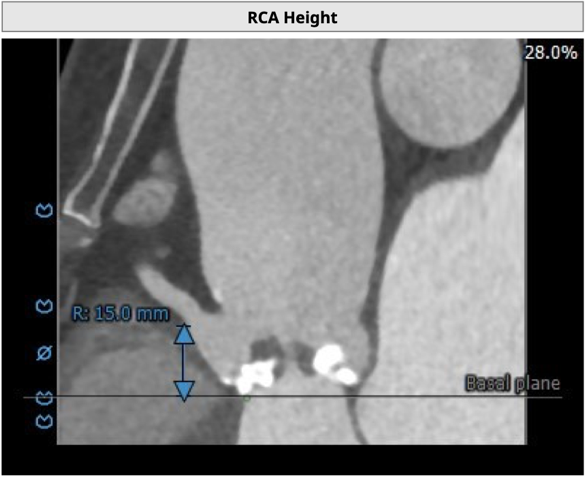

左冠开口高度8.6mm,右冠开口高度15.0mm,左冠高度偏低,左冠瓣瓣尖钙化明显,根据瓦氏窦内径和瓣叶长度综合判断,左冠存在较高堵塞风险;左心室后壁增厚。